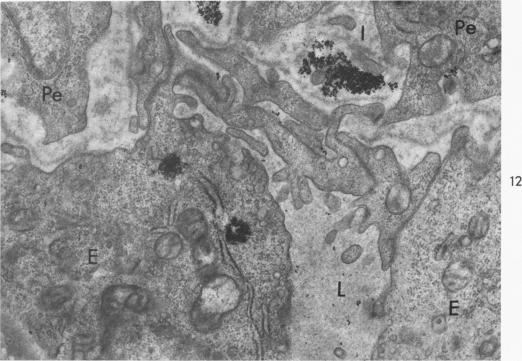

The pathogenesis of corneal edema induced by Tween 80.

Am J Pathol. 1967 Dec;51(6):977-99.